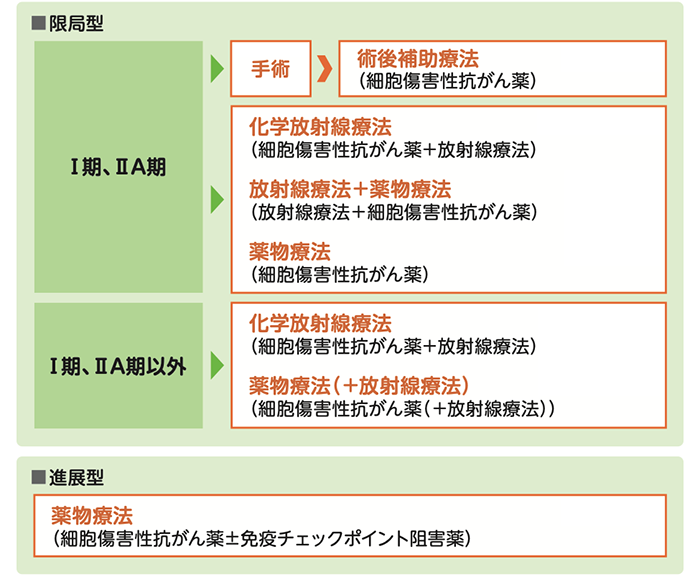

限局型と進展型の違い

がんの広がりによって限局型と進展型に分類され、それぞれに適した治療方法が選択されます。

限局型

<状態>

がんが放射線療法の可能な範囲にとどまっている状態をいいます。

- ・がんが原発巣(最初にがんができたところ)と同じ側の肺にとどまっており、胸腔や心臓に「悪性胸水」「悪性心嚢水」と呼ばれる体液がみられない場合。

- ・同じ側のリンパ節転移(鎖骨上、縦隔、肺門リンパ節)と、反対側の縦隔リンパ節への転移がみられる場合も含む。

限局型小細胞肺がんの病変の範囲

進展型

<状態>

放射線を照射できる範囲を越えてがんがひろがっている状態をいいます。

- ・肺以外の臓器に転移している場合

- ・原発巣以外の肺に転移している場合

- ・悪性胸水、悪性心嚢水がたまっている場合

- ・原発巣と反対側の肺門リンパ節に転移している場合

進展型小細胞肺がんの病変の範囲

小細胞肺がんの治療

小細胞肺がんの治療は「限局型」か「進展型」かによって異なります。基本的には薬物療法と放射線治療が中心で、限局型のごく早期の場合は、手術も選択されることがあります。

限局型小細胞肺がんの治療

- ・化学療法(抗がん剤)と放射線治療を併用する「化学放射線療法」が中心となります。

- ・ごく早期の場合、手術のみ、あるいは手術後に薬物療法を追加する治療がおこなわれることもあります。

- ・化学放射線療法によりほぼがんが消失したと判断された場合、脳への転移を予防するために脳全体に放射線を照射する「予防的全脳照射」がおこなわれることもあります。

進展型小細胞肺がんの治療

- ・薬物療法が中心で、化学療法(抗がん剤)が中心となります。免疫チェックポイント阻害薬と併用することもあります。使用する薬剤は患者さんの体の状態よって異なります。

- ・がんそのものの治療ではなく、がんによる痛みなどの症状をやわらげることを目的に放射線療法(緩和的放射線治療)がおこなわれることもあります。